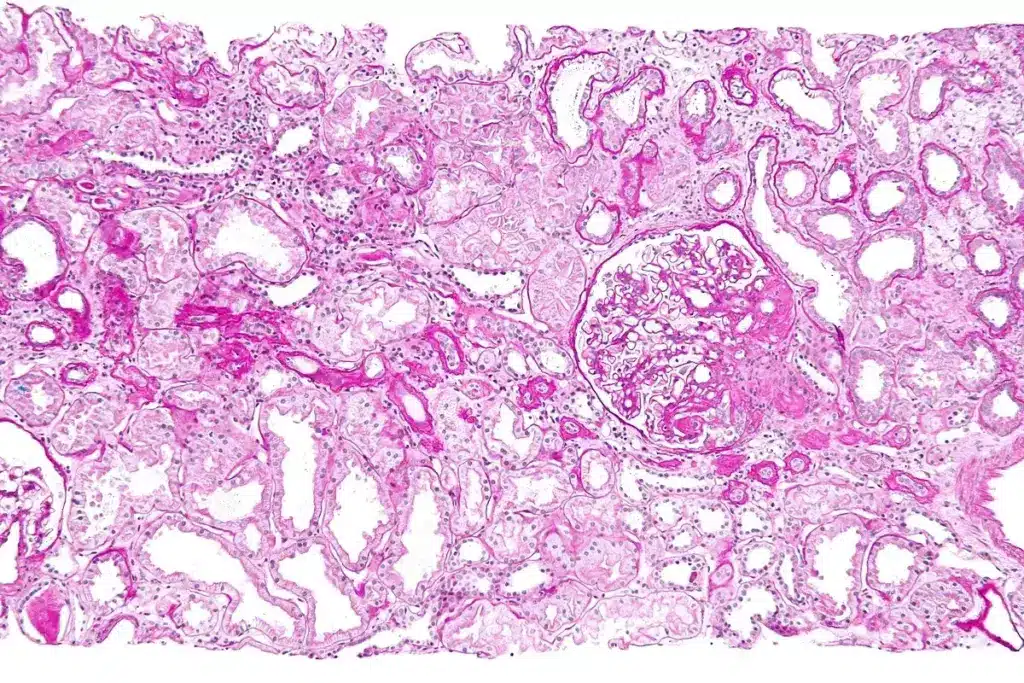

Kidney biopsies are key in diagnosing and managing kidney diseases. They give insights into the kidney’s health. A biopsy involves taking a small kidney tissue sample for microscopic examination.

A kidney biopsy is a procedure to get a small kidney tissue sample. It helps diagnose kidney diseases, assess damage, and guide treatment.

Tissue Sample Collection and Preservation

When the needle is in the right spot, a tissue sample is taken. The sample is kept in a special medium to keep it good for looking at under a microscope. The tissue sample collection is very important for getting an accurate diagnosis.